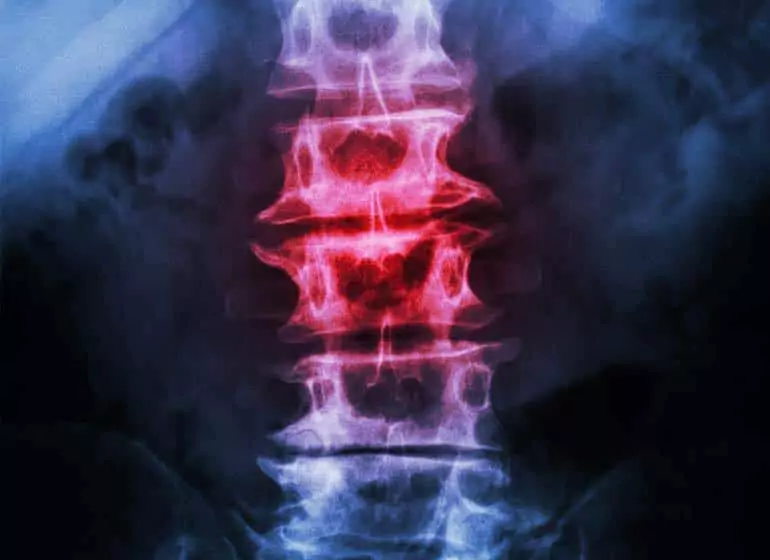

Spondylosis is a medical term that refers to a general degradation of the vertebrae of the spinal column due to any cause, but most often due to age and time. More specifically, it refers to the emergence of osteoarthritis in the spinal column due to the drying out of the discs within. As the discs dry out and thin, other signs may emerge as well, like:

Your first visit to the Better Health office will begin with a frank discussion of your symptoms with an Anchorage-based chiropractor. He/she will also go over your medical history – both personal and family. From there, you’ll receive a thorough exam which may or may not involve imaging (MRI, x-ray, what-have-you).